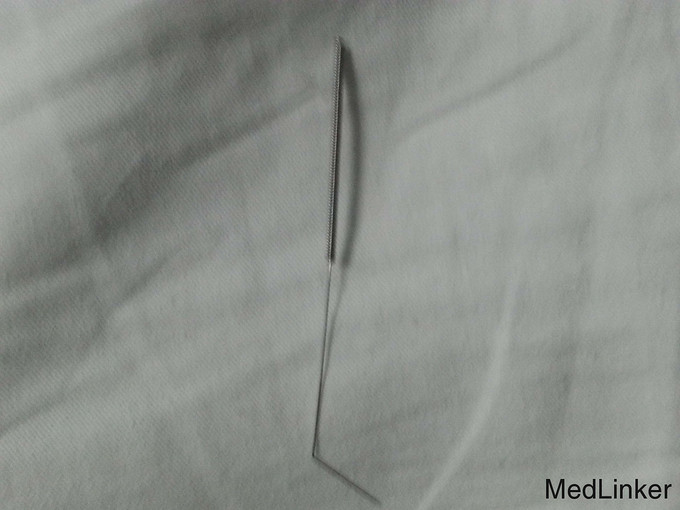

患者,男性,13岁,因尿道异物8天入院。有腰腹部隐痛不适症状,有排尿不适症状,无明显血尿及排尿困难病史。既往无手术史。

体检:双肾区、输尿管行径区、膀胱区无压叩痛、未及包块。阴茎根部腹侧阴囊内可触及一条索状质硬异物,有明显触痛。辅助检查:岳池县罗渡中心卫生院(2015-9-9)盆腔X线片示会阴部阴囊内一针样异物。

诊断:1、尿道内针样异物伴尿道阴囊穿刺伤。 治疗:行输尿管镜检异物取出术,术后安置尿管一周

讨论:少年异物癖放置针样异物致尿道内非常罕见,从尿道内顺针穿刺方向逆向将针取出可最大限度减少尿道损伤。随访:术后一月复诊无排尿困难及尿道狭窄发生。